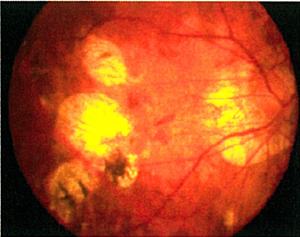

老年性(圖4)及深近視性(圖5)黃斑點退化的脈絡膜新生血管膜之治療

光動力療法曾經是老年性及深近視性黃斑點退化的脈絡膜新生血管膜的主要治療,惟此治療僅可維持已衰退的視力,或遏止視力進一步退化。現時,眼內藥物注射(包括Lucentis、Avastin、Eylea及類固醇)是常見治療方法,能讓大部份病人回復一定程度的受損視力。而且注射過程安全,甚少出現副作用。

![]() 圖4:老年性黃斑點退化-出血 |